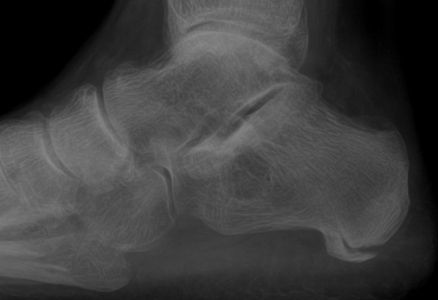

Query: Calcaneal Avulsion Fracture

This is a 37 year old patient who was walking rapidly yesterday. He said he turned to change directions and felt a horrible pain in his heel. He has a significant medical history of a motorcycle accident approximately a year ago with multiple fractures of the contralateral limb, but there was no trauma to the limb involved today.

Calcaneal avulsion fracture |

It's rare to see avulsion fractures of the plantar fascia attachment. Achilles attachment avulsions are more common in about 1% of calcaneal fractures. The question is surgical repair or no surgical repair? It is almost asking for a percutaneous screw.